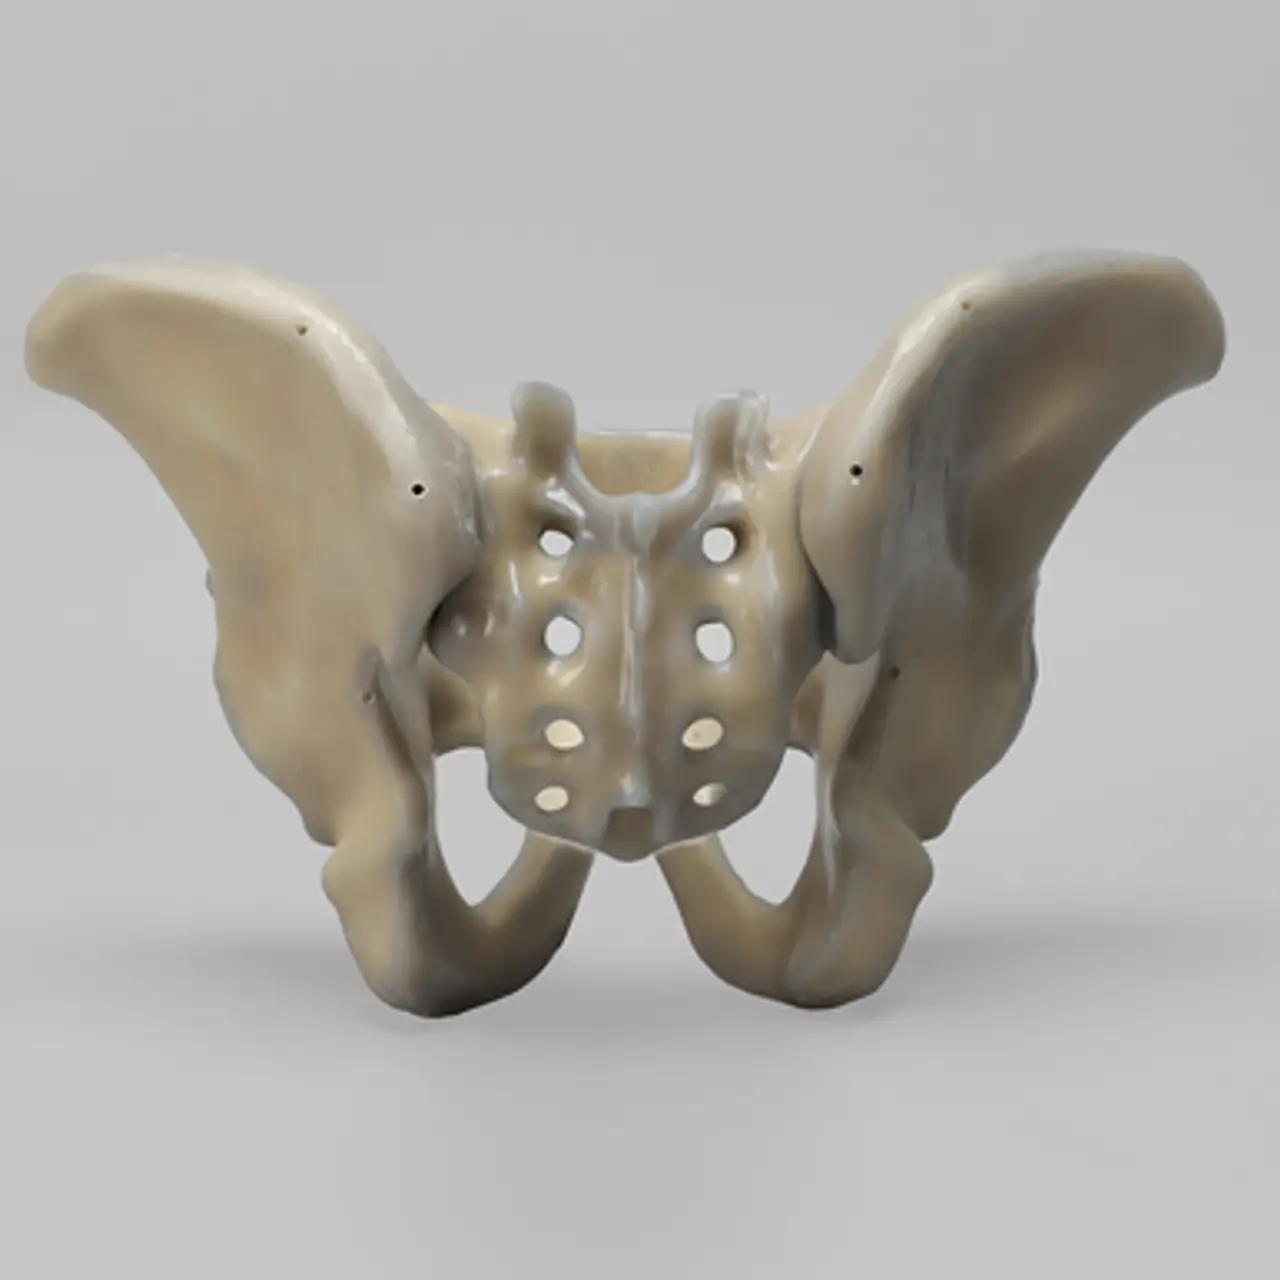

人工骨骨盆模型3415

人工骨模型,完整男性骨盆,absolute™ 第四代,17 PCF 实心泡沫芯,大号

用于力学测试的完整男性骨盆

我们的 absolute™ 骨模型 精确模拟人体骨骼的结构与力学特性,能够帮助科研人员和医疗器械企业在开发与审批过程中,轻松且经济地再现载荷与运动场景。该模型特别适用于生物力学研究、医疗器械测试及教学演示。

| 解剖部位 (Anatomy) | 骨盆 – 完整 |

| 模型类型 (Model Type) | absolute™ 骨模型 |

| 材料 (Material) | absolute™ |

| 尺寸 (Size) | 大号 |